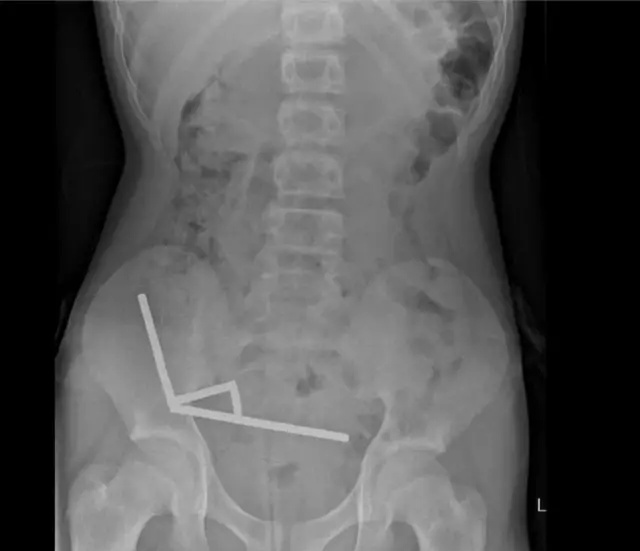

Οι ακτινογραφίες αποκάλυψαν στη συνέχεια ότι οι μαγνήτες – οι οποίοι έχουν απαγορευτεί στη Νέα Ζηλανδία από το 2013 – ήταν συνδεδεμένοι σε «τέσσερις γραμμικές αλυσίδες» μέσα στα έντερα του, περιορίζοντας τη ροή του αίματος και του οξυγόνου στην περιοχή, προκαλώντας τον θάνατο του ιστού.